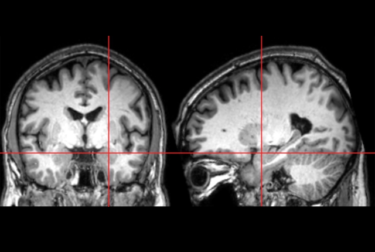

The crosshairs in this photo focus on the amygdala. New research has found that this area of the brain grows too rapidly in the first year of life in babies who go on to develop autism.Dr. Stephen Dager/U. of Washington

Researchers have long known the amygdala is significantly larger in school-age children diagnosed with autism, but it was unknown precisely when that enlargement occurs. Now, for the first time, researchers from the Infant Brain Imaging Study (IBIS) Network, which includes the University of Washington, used magnetic resonance imaging (MRI) to demonstrate that the amygdala grows too rapidly in infancy. Overgrowth begins between 6 and 12 months of age, before the characteristics of autism fully emerge, potentially enabling the earliest identification of this condition.